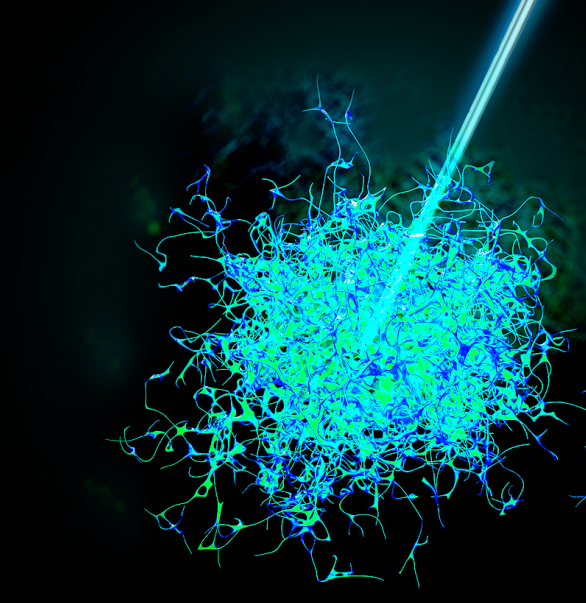

今天,我们把肿瘤的内部「融穿」了